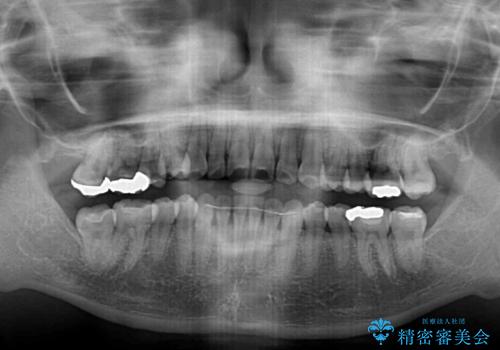

- 上下前歯のデコボコを気にして来院された患者様です。

インビザラインによる上下歯列の側方拡大と後方移動、IPR(歯と歯の間を削る)にるスペースの獲得により歯列を整えることとしました。

右上の小臼歯は歯根癒着をしており、様々な方法を試みるも動かすことができませんでした。

それでも奥歯のかみ合わせに不自由はなく、歯列をきれいに整えることができました。